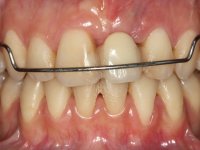

The surgical implant exposure and the healing screw placement proved to be a negative surprise regarding its position. Since the proposed removal of the implant was refused, we advanced to its provisional rehabilitation. An open tray impression technique was done, and a screwed abutment with a coronal and gingival component and an acrylic crown were made in the laboratory, using these two components. The provisional crown was placed in the mouth until a final decision was made. Six years passed before the patient returned to the clinic with an abscess on tooth 1.1. The choice to remove teeth 1.1 and 2.2 was made, to create a provisional 3-element bridge with a net to be adhered to the adjacent teeth. Surgery was planned and performed, placing the two implants at the site of 1.1 and 2.2, and the implant at the 2.1 site was cut with the objective of submerging it, while adequate tissue regeneration was performed (Surgical Work performed By Dr. Manuel Neves). During osseointegration, the patient used the fixed provisional bridge. A first impression was made for confection of a zirconia screwed provisional bridge, which worked the soft tissues for twelve weeks. The definitive impression was made with the individualisation of custom impression copings. Final rehabilitation was done with ceramized abutments, and also a bridge with zirconia infrastructure and ceramic cover. Due to the inclination of the implant placed at the site of tooth 1.1, the bridge required cemented fixation.